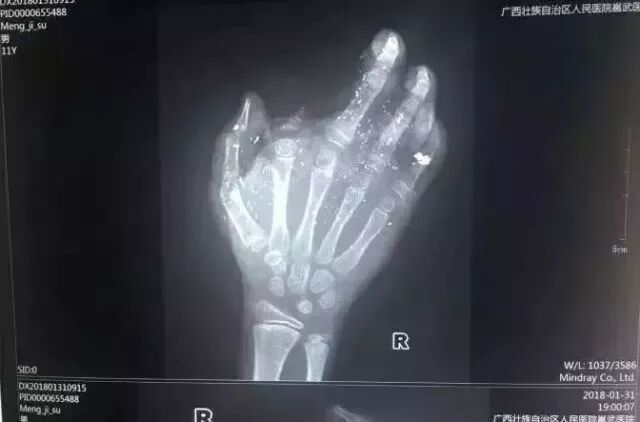

手機爆炸起火一家四口遭遇不測 湖南有一家四口,遭遇了手機爆炸起火。事發(fā)當晚,一家四口被送進醫(yī)院,遺憾的是兩個孩子傷勢嚴重,最終都沒能挽回生命。 爆炸的現(xiàn)場床頭一片焦黑,被褥都被燒成了灰,旁邊的椅子也只剩下鐵架子了,現(xiàn)場一片狼藉。 其中的男主人和女主人睡前都有玩手機的習慣。發(fā)生爆炸時手機就在床頭充電,手機爆炸引起大火,熟睡的一家人根本就來不及反應,瞬間就被大火所吞噬。 手機爆炸致男孩手掌被炸傷 2018年1月31日,廣西發(fā)生一起手機爆炸事件,一名年僅12歲的小男孩手掌被炸得血肉模糊,右手食指被炸沒了,拇指、中指、無名指也都炸傷,失去了供血,手掌皮膚被炸得稀爛。 經(jīng)CT檢查,右眼內(nèi)有2塊手機碎片。據(jù)了解,手機之前出現(xiàn)過充電時發(fā)熱現(xiàn)象,但家長當時未在意。 手機爆炸致后腦勺鮮血淋漓 2018年6月,武漢的李先生,晚充著電玩手機,后來睡著了,半夜手機爆炸,后腦勺被炸的鮮血淋漓。